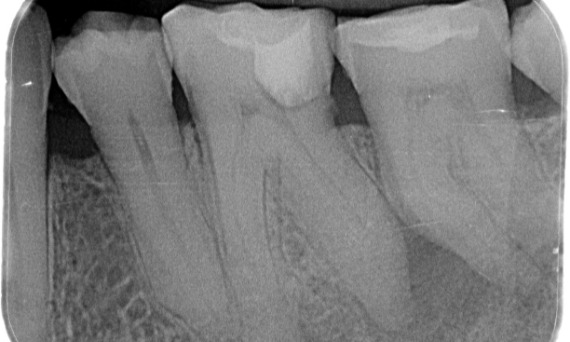

Antes: Tras el examen, hubo una lesión de caries relacionada con el primer molar inferior derecho. El examen radiográfico reveló la proximidad de la lesión a la bocina pulpar y, al combinarla con la queja principal, se concluyó un diagnóstico final de pulpitis irreversible crónica.